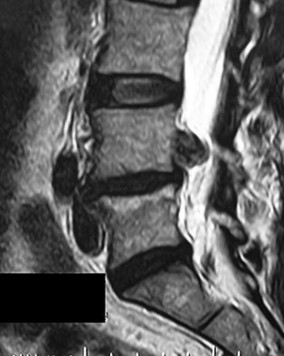

Question 37

On a sagittal MRI of the lumbar spine, a vertebral body endplate adjacent to a degenerated disc shows hypointense signal on T1-weighted images and hyperintense signal on T2-weighted images. This finding corresponds to which Modic type, and what does it pathologically represent?